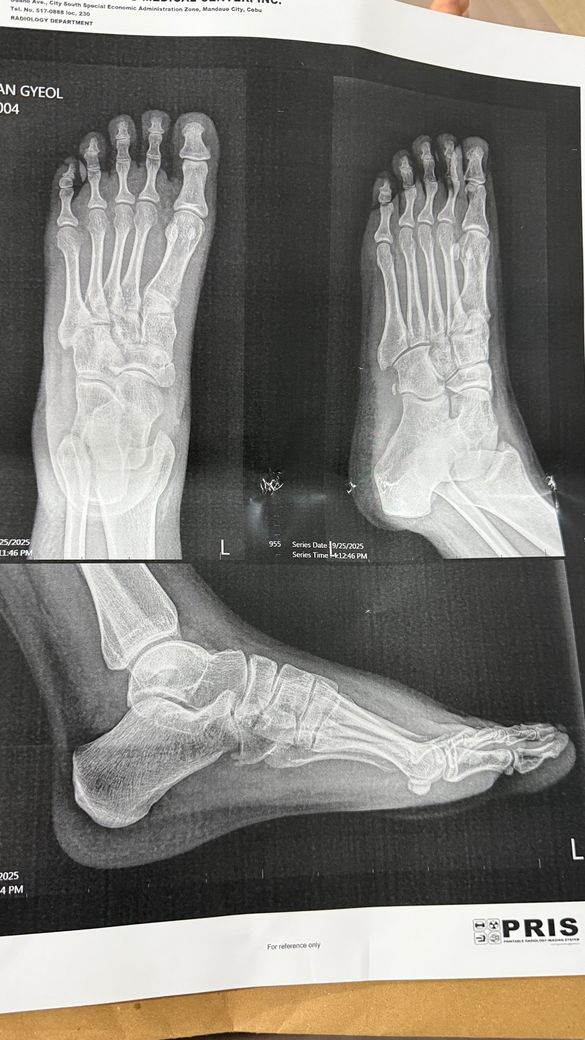

계단에서 넘어져서 발목 인대를 다쳤는데 제가 해외에 있어서 제대로 진료를 못 받고 깁스를 착용중입니다. 5일 지났는데 발목부터 발가락까지 멍이 들었고 아직 붓기가 심합니다. 해외 병원에서는 그냥 발목 인대가 늘어난거라고 하는데 상태가 너무 안좋아서 혹시 인대가 파열된건지 걱정이 됩니다.알 수 있을까요? X-ray 사진 첨부합니다.

엑스레이는 뼈를 확인하는 검사라 인대 손상을 직접적으로 알 수 없습니다. 때문에 MRI나 초음파를 확인하시는게 좋은데요. 멍가 붓기가 발목부터 발가락까지 심하게 번졌다면 단순 염좌보다 부분 파열 이상일 가능성이 높습니다. 감사합니다.

엑스레이는 뼈의이상유무를 판단하는검사이기때문에 좀더 정확한 진단을 위해서는 MRI와같은 정밀검사가 필요할수있습니다

x-ray 검사로는 발목인대파열 정도를 정확히 확인하기는 힘듭니다. 발목인대파열 정도를 정확히 알기 위해서는 초음파나 MRI검사가 필요합니다.

사진으로 보아서는 발목인대 손상이 심해보이며 손상정도와 관리에 따라 다를 수는 있겠지만 2-3주 정도는 깁스를 착용하셔야 할 것으로 보입니다.

엑스레이상에서는 연부조직인 인대의 싱태를 확인하는데 어려움이 있습니다.